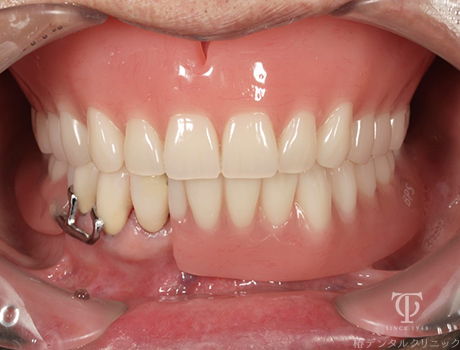

Case02

- 症状

- 右上の痛み

- 治療期間

- 約2年

- 治療費用

- (上顎)メタルボンド:132,000円×7本

(上顎)部分床義歯:550,000円

(下顎)インプラント治療:473,000円×3本

(下顎)オールセラミッククラウン:110,000円×4本

右上の歯肉の痛みで来院されました。歯周病やかみ合わせに問題があり患者様と相談の上、インプラントと部分床義歯にてかみ合わせを再構築しました。

【リスク・副作用】

インプラント治療後、痛みや違和感、出血、腫れなどが出る事があります。喫煙者、糖尿病などの方の場合、歯が生着しない場合があります。入れ歯を清潔に保たないと虫歯や歯肉炎、歯周病になるリスクがあります。